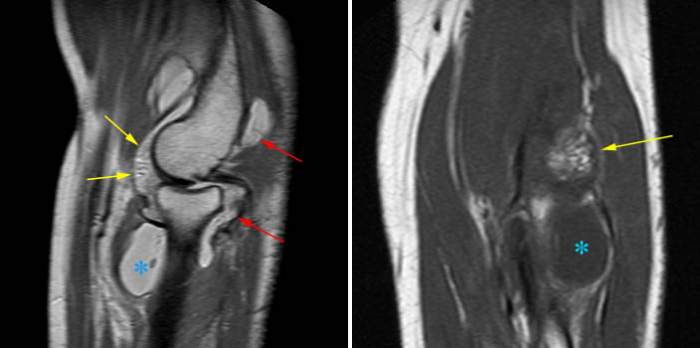

Рисунок 9. Древовидная липома локтевого сустава (желтые стрелки) — редкая локализация для данной патологии. Красные стрелки обозначают синовит (с проявлениями пролиферации) сустава, синяя звездочка — выпот.

Рисунок 9. Древовидная липома локтевого сустава (желтые стрелки) — редкая локализация для данной патологии. Красные стрелки обозначают синовит (с проявлениями пролиферации) сустава, синяя звездочка — выпот.